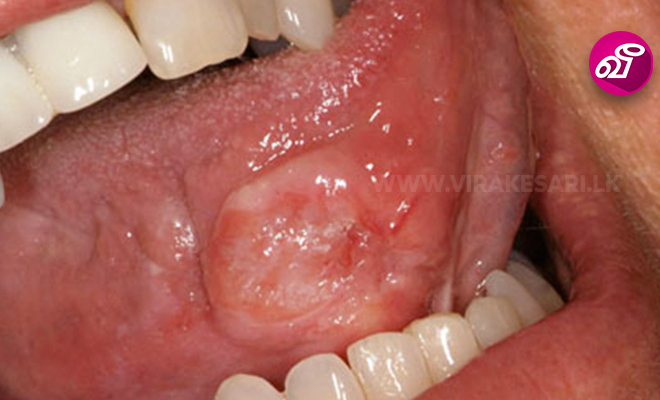

மூளையில் ஏற்படும் கட்டிகள் மற்றும் புற்றுநோய் ,மார்பக புற்றுநோய், குழந்தைகளுக்கு ஏற்படும் புற்றுநோய், கண், உணவு குழாய், தலை, கழுத்து, கல்லீரல், நுரையீரல், கணையம், பிட்யூற்றரி, புராஸ்டேட், முதுகெலும்பு , மண்டை ஓட்டின் அடிப்பகுதி... ஆகியவற்றில் ஏற்படும் புற்று நோய்களுக்கு சிகிச்சை அளிப்பதில் இந்த புரோட்டான் பீம் தெரபி முழுமையான நிவாரணம் அளிப்பதாக வைத்திய நிபுணர்கள் தெரிவிக்கிறார்கள்.

புரோட்டான் கற்றைகளை புற்றுநோய் பாதித்திருக்கும் பகுதியில் வைத்திய நிபுணர்கள் துல்லியமாக நேரிடையாக செலுத்தி அந்த செல்களை அழிக்கிறார்கள்.